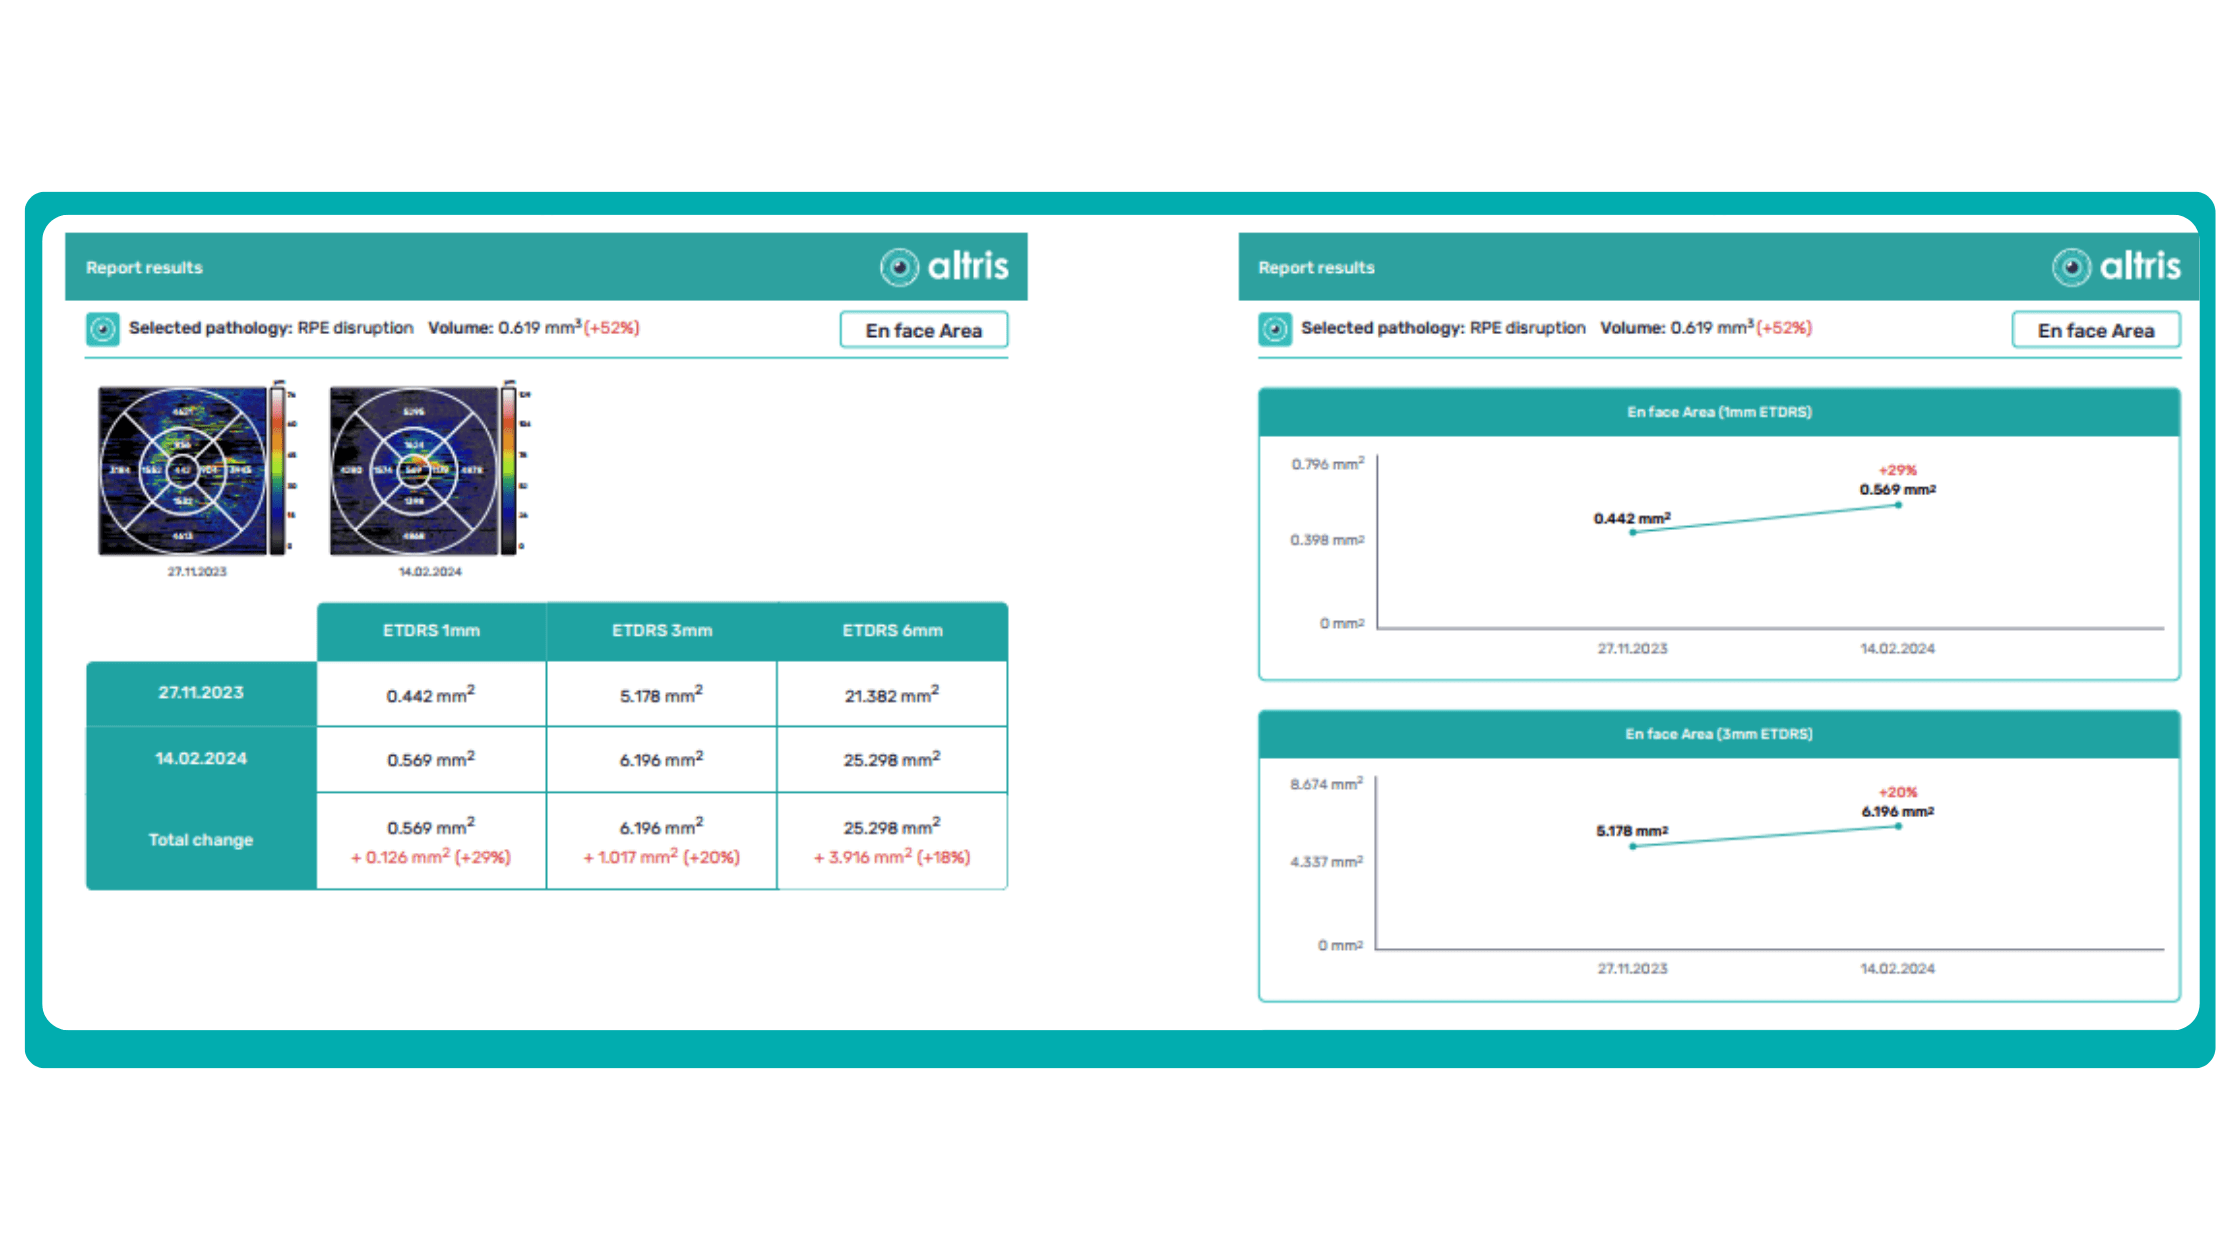

To illustrate the point, here is a handwritten referral compared to one of the types of customised OCT report from the Altris AI system, a platform that automates AI-powered OCT scan analysis for 70+ pathologies and biomarkers. This screenshot, in particular, shows segmented retina layers and highlights biomarkers of Dry AMD alongside a comparison of the patient’s macular thickness over visits.

Imaging biomarkers are a particularly attractive option for clinical practice due to their non-invasive and real-time nature. Quantitative measurements of retinal thickness, fluid volume, and other biomarkers relevant to diseases like diabetic retinopathy and age-related macular degeneration aid in treatment monitoring.

OCT reports with customized measurements and selected biomarkers, retinal layers, or segments allow for precise focus on treatment monitoring and patient response to therapy. This personalized approach enhances clinical decision-making by highlighting each case’s most relevant information.

Let’s explore how this applies to a clinical case, such as monitoring a patient with Wet AMD during follow-up visits.

Data demonstrates that OCT findings can reveal the onset or progression of neovascular AMD before a patient reports new symptoms or changes in visual acuity. In fact, OCT images are reported to have the best diagnostic accuracy in monitoring nAMD disease states. This underscores the importance of key OCT findings or biomarkers in personalizing anti-VEGF treatment, achieving disease control, and reducing monitoring burdens.

Central Retinal Thickness emerged as one of the earliest OCT biomarkers used as an outcome measure in clinical trials for nAMD.

However, due to confounding factors, CRT’s use in outcome-based assessments of nAMD varies. Thus, it is essential to evaluate additional morphological changes alongside retinal thickness and their relationships with functional outcomes.

It has been reported that OCT images have the best diagnostic accuracy in monitoring nAMD disease states.

Another finding that is correlated with a worsening VA due to the associated photoreceptor defects is any damage to the four outer retina layers, including the RPE, interdigitation zone (IZ), ellipsoid zone (EZ), and external limiting membrane band (ELM).

OCT is a valuable imaging tool for visualizing subretinal hyperreflective material (SHRM). It can automatically identify and quantify SHRM and fluid and pigment epithelial detachment to calculate the overall risk of worsening visual outcomes associated with SHRM.

Subsequent follow-up visits will then display the most relevant picture, highlighting the most pertinent biomarkers for tracking a particular pathology (wet AMD in our example) and comparing their volume, progression, or regression through visits.

Another helpful option is retinal layer segmentation, which focuses solely on the retinal layers of interest for the specific case.

This level of customization empowers clinicians with a comprehensive yet targeted view of the patient’s condition. It saves time from manually detecting anomalies on scans and facilitates informed decision-making and personalized treatment plans.